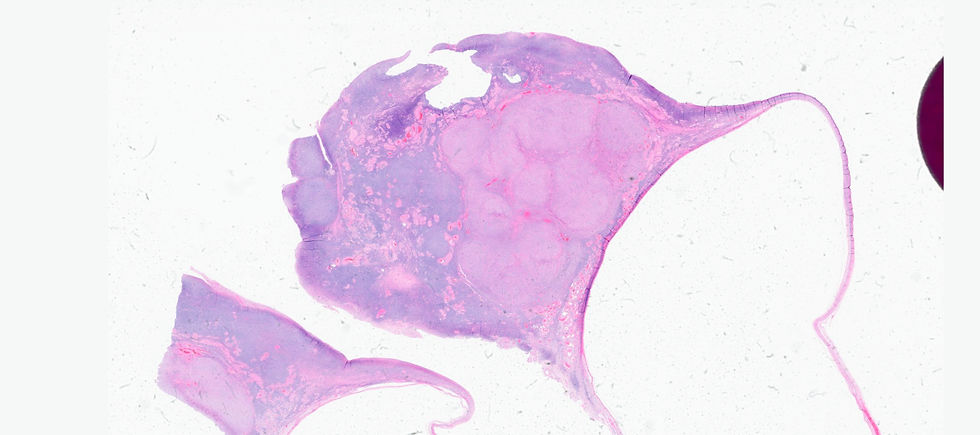

A 50-year-old women presented with abnormal uterine bleeding and she was found to have a large ovarian mass.

Before showing the IHC, putting the tumor into sex-cord stromal category is correct. However, the large solid nest architecture with irregular spindle to oval nuclei may clue you in a certain entity.

The final answer is F. Adult granulosa cell tumor (AGCT). AGCT can show various morphological patterns however, the most common pattern is diffuse, but cells may be arranged in cords or trabeculae; large solid nest, or forming microfollicular pattern with Call–Exner bodies. Nuclei groove is a reliable feature but it is not always seen. In this case of luteinized tumor show abundant eosinophilic cytoplasm and often lack nuclear grooves. The tumor cells are positive for FOXL2, calretinin, inhibin (although staining may vary in distribution and intensity), and SF1. Reticulin surrounds groups of cells rather than single cell in thecoma or fibroma.